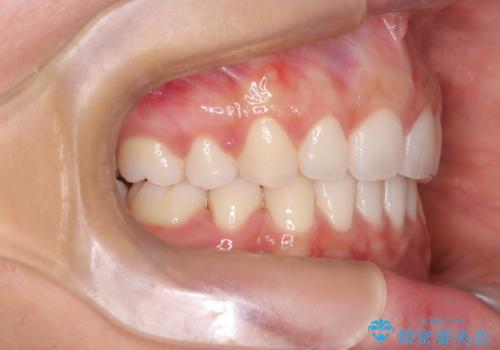

3. 【審美ワイヤー】口元を下げたいの治療後